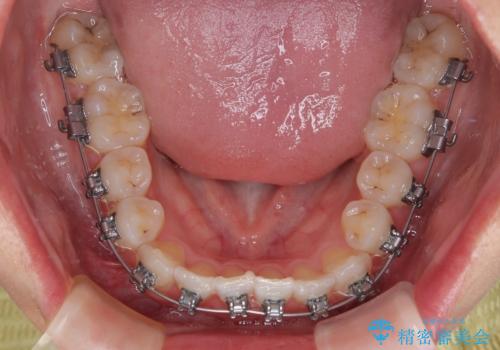

- メタルブラケット

装置の外見を気にしていましたが、短期間で治療を終えることができるだろうと伝えると、安価であるメタルブラケットを選択されました。